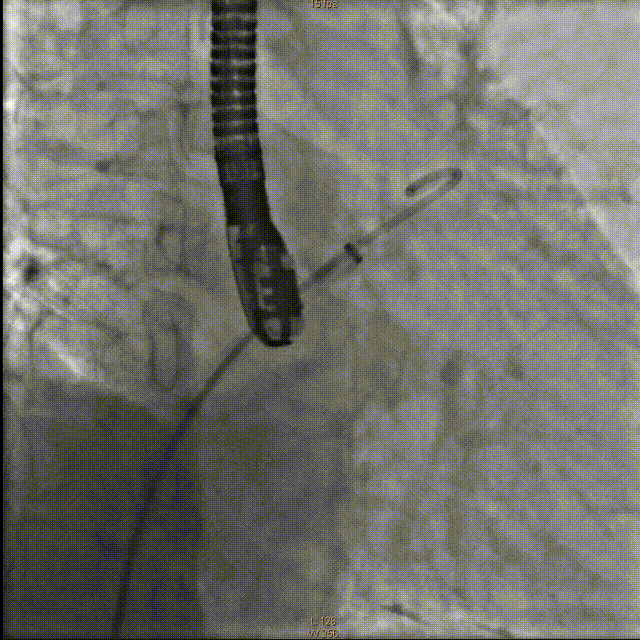

将传输外鞘推送至左心耳开口,结合术前及术中超声检测结果,选择直径26mm左心耳封堵器。严格排气后送入左心耳封堵器,在食道超声及DSARA30°+CAU20°透视下精确定位左心耳封堵器固定盘,造影示位置及封堵良好,透视下释放封堵盘并牵拉,造影及超声检测未见明显漏肩及侧漏,固定盘及封堵盘稳定,贴合左心耳开口好。

释放固定盘并造影

覆盖盘释放并造影

牵拉实验固定稳妥,无明显心包积液,透视下释放左心耳封堵器于左心耳。退出输送鞘管至右房测右房压12/5mmHg:撤出传送钢丝及血管穿刺鞘。

牵拉试验

释放封堵伞